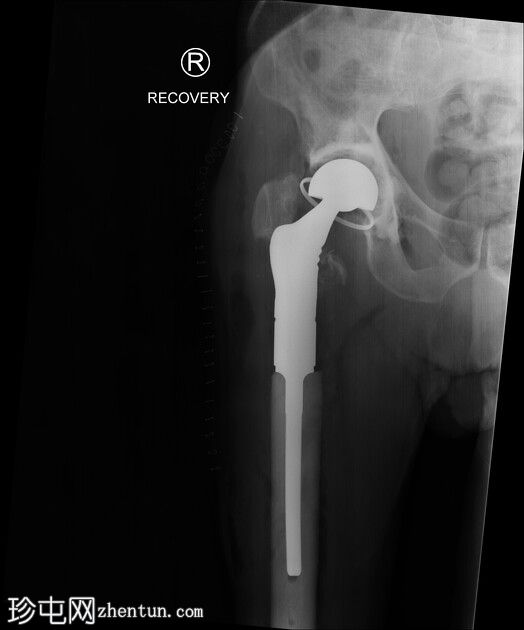

术中恢复期影像学检查:股骨髓内钉固定穿过小转子水平处已知的溶骨性病变。无金属部件损坏或假体周围骨折。

患者随后接受了股骨近端置换术。